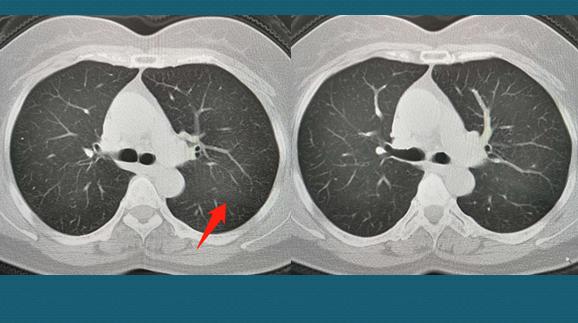

虽然医生这么安抚,病人心里还是七上八下,好在输液一次之后咳嗽症状就好转了。7天后回来复查CT,大部分吸收了:

这下总算是心里石头落了地了,年前就出院了!